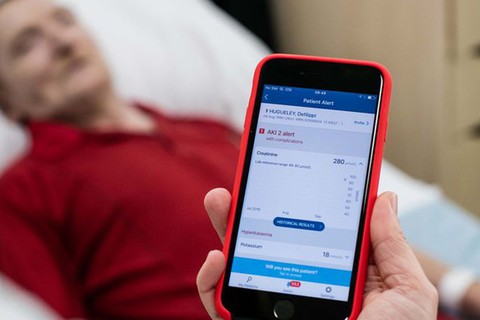

Công ty DeepMind cũng đã thiết lập ứng dụng Streams dành cho các bác sĩ. Bác sĩ sử dụng ứng dụng này sẽ tự động nhận được bệnh án, như vậy giảm thời gian chờ đợi của người khám bệnh và giảm thủ tục rườm rà.

Ứng dụng Streams của Công ty DeepMind giúp bác sĩ biết bệnh án nhanh nhất - Ảnh: DEEPMIND